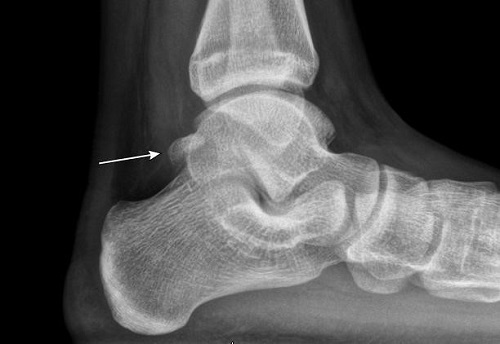

Se inicia tratamiento con antiinflamatorios no esteroideos, frío local y reposo relativo. Se realiza radiografía de tobillo que muestra os trigonum como variante anatómica (Fig. 1). Ante la cínica compatible con Síndrome del Trígono y la presencia de dolor pese al primer escalón terapéutico se deriva a traumatología que confirma el diagnóstico y deriva a rehabilitación.

Figura 1. Os trigonum, persistencia del centro de osificación lateral en la cara posterior del astrágalo

La persistencia del centro de osificación lateral en la cara posterior del astrágalo después de la maduración esquelética da lugar al os trigonum, el dolor se produce por la compresión ósea y de tejidos blandos en el espacio tibiocalcáneo posterior.